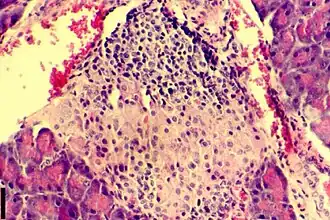

Дефицит инсулина в организме развивается вследствие недостаточной его секреции β-клетками островков Лангерганса поджелудочной железы.

- Активный аутоиммунный инсулит. Титр антител высок, уменьшается количество β-клеток, снижается секреция инсулина.

- Клиническая манифестация диабета, в том числе с возможным эпизодом «медового месяца» (периода ремиссии в развитии диабета, который характеризуется повышением количества инсулина вырабатываемого бета-клетками). Секреция инсулина резко снижена, так как погибло более 90 % β-клеток.

- Полная деструкция β-клеток, полное прекращение секреции инсулина.

Исследователи из Калифорнийского университета в Сан-Франциско смогли превратить человеческие стволовые клетки в зрелые инсулин-продуцирующие клетки (бета-клетки). Замена этих клеток, которые разрушаются у пациентов с диабетом T1, долгое время была мечтой о регенеративной медицине. Ученые не могли понять, как можно вырастить бета-клетки в лабораторных условиях так, чтобы они работали так же, как у здоровых людей. Ключом к получению искусственных бета-клеток стал процесс их формирования в островки Лангерганса у здорового человека. Авторы метода воспроизвели этот процесс в лабораторных условиях: они искусственно разделили частично дифференцированные стволовые клетки поджелудочной железы и преобразовали их в островковые кластеры. После чего развитие клеток ускорилось. Бета-клетки стали реагировать на уровень сахара в крови сильнее, чем зрелые инсулин-продуцирующие клетки. Также вся «окрестность» островка, включая менее изученные альфа- и дельта-клетки, начали развиваться так, как никогда не получалось сделать в лабораторных условиях.[24]